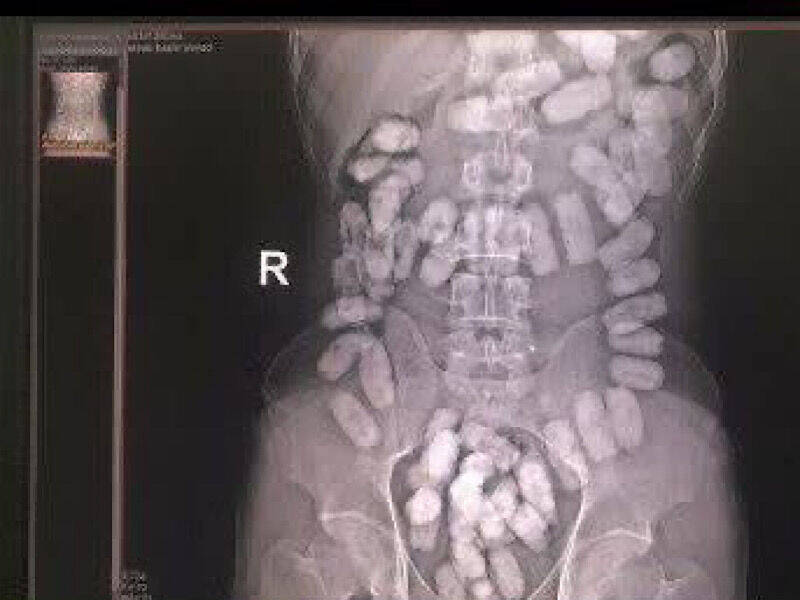

به گزارش مشرق، سردار مجید شجاع افزود: مرزبانان ایست و بازرسی 17 شهریور هنگام بازدید و بازرسی مسافران در قسمت ورود به کشور، تعداد 33 بسته مواد آب بندی شده به وزن 372 گرم مواد مخدر از نوع هرویین که در معده جاساز شده بود، را از یک تبعه افغان کشف کردند.